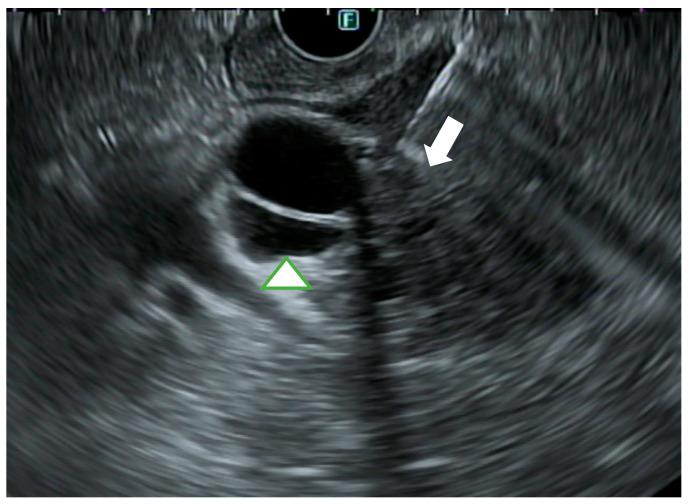

This review aims to focus on what we know about the management of biliary strictures of unknown etiology, especially exploring our diagnostic armamentarium in the setting of indeterminate biliary strictures. Presently, this is a current issue that has a relevant impact both on patient prognosis, often delaying diagnosis, and on overall costs associated with repeating diagnostic procedures, sometimes performed with very expensive devices. We also focus on current biliary drainage approaches, providing an overview of therapeutic options, endoscopic or not.

本综述旨在聚焦于我们对病因不明的胆管狭窄的管理所知,尤其探索在不确定胆管狭窄情况下的诊断手段。目前,这是一个当前的问题,对患者预后(常常延误诊断)以及与重复诊断程序相关的总体成本都有相关影响,有时这些诊断程序使用非常昂贵的设备进行。我们还关注当前的胆管引流方法,概述治疗选择,无论是否为内镜治疗。